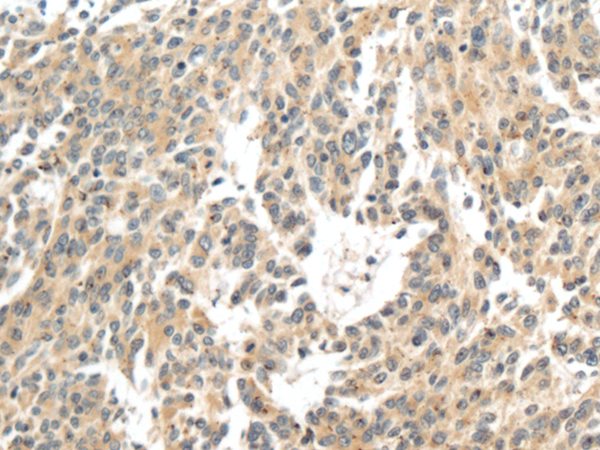

ELISA, IHC |

IHC positive control: |

Human colorectal cancer |

IHC Recommend dilution: |

100-300 |